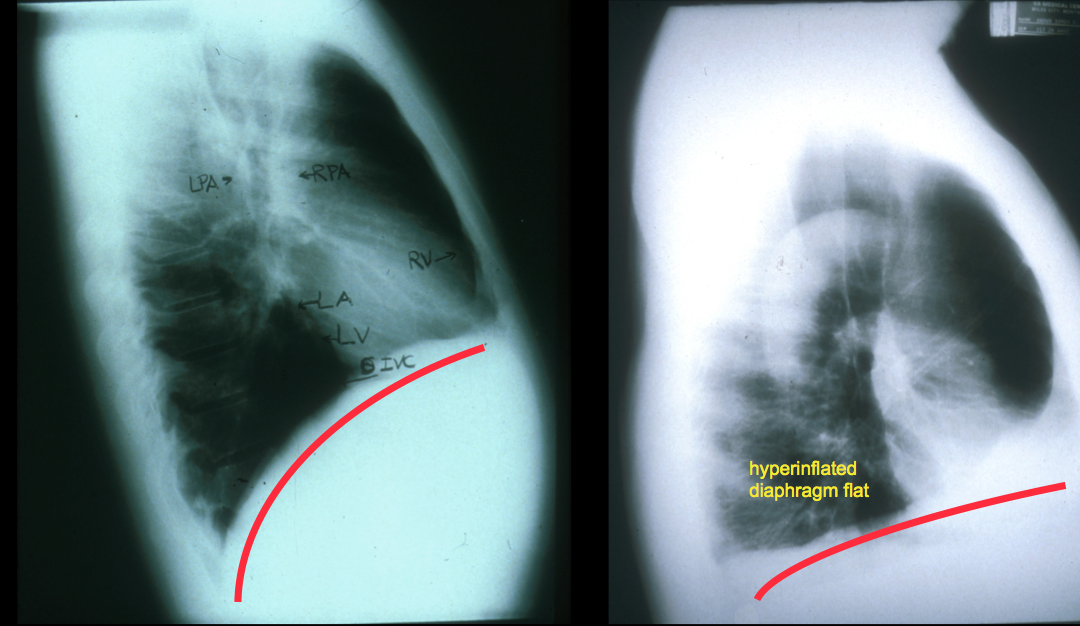

How does diaphragm change in obstructive disease

diaphragm gets flattened because pressure builds up and pushes down

How does hyperinflation and obstructive disease affect

RV

ERV

IC

incr RV

incr ERV

incr FRC

decr IC

How does flattening of diaphragm in obstructive disease affect inspiration?

why?

less inspiratory pressure because incr radius of curvaure

so diaphragm must generate more tension

Signs of acute asthma

Hyperinflation

Unable to exhale fully before next breath = incr TLC

Decr tension by shortened diaphragm